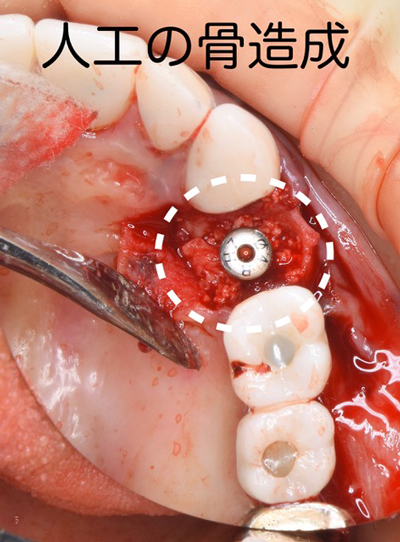

患者様は、迷わずインプラントを選択されました。抜歯と同時にインプラントの移植と自己血液を用いた骨の造成再生術を行われました。

腫瘍が骨を大きく溶かしていましたので、欠落した部分にCGFに人工の骨を混ぜ合わせ、骨の再生をインプラントの移植と同時に試みました。

手術直後の状態です。

患者様は静脈麻酔鎮静法(無料)を受けながらの施術でしたので、手術中の記憶は殆ど無かったとのこと。